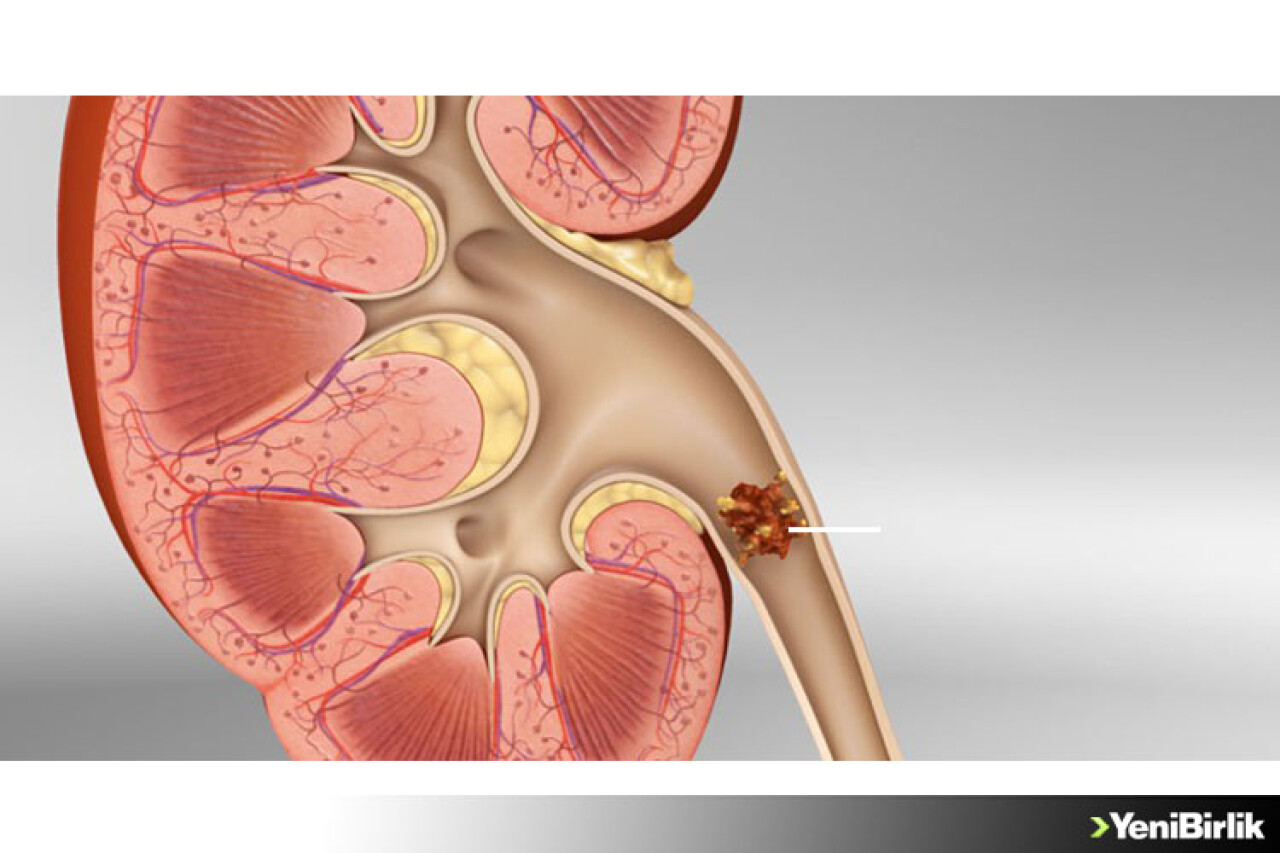

Taşlar idrar ile atılamadığı zaman böbreklerden mesaneye kadar idrar yolunun herhangi bir bölgesini etkileyebiliyor. Memorial Sağlık Grubu Medstar Topçular Hastanesi Üroloji Bölümü'nden Op. Dr. Adil Güçlü Güçal, taş hastalığı ve tedavisi hakkında bilgi verdi.

İdrar, kristallerin bir araya gelip büyümesini baskılayan kimyasallar içerir. Eğer kristaller yeterince küçük ise idrar kanalından tıkanıklık yapmadan geçer ve fark edilmeden vücuttan atılır. Ancak bu kristaller bir araya gelerek büyür ve taş oluşur ise doğal yolar ile vücuttan atılamaz. Vücutta oluşan farklı taş tipleri bulunmaktadır. Bunlardan en sık karşılaşılanlar kalsiyum taşları, enfeksiyon taşları, ürik asit taşları ve sistin taşlarıdır.

Şikayeti olan hastalara gerekli kan ve idrar tahlilleri yapılır. Grafi, intravenöz pyelografi, ultrasonografi, bilgisayarlı tomografi radyolojik gibi görüntüleme yöntemleri kullanılarak taş hastalığı tespit edilir ve taşın yeri, boyutu, böbreğe zarar verip vermediği bilgileriyle tedavi seçenekleri belirlenir. Tedavi ise taşın türü, nedeni, boyutu ve yerleşim yerine göre değişir. Pek çok böbrek taşı girişimsel tedaviler gerektirmez. Sıvı tüketiminin artırılması, ağrı kesici ilaçlar ve taşın düşmesini kolaylaştıran bazı tedaviler ile 5 mm'nin altındaki taşların yaklaşık %98'i düşürülebilir. Tekrarlayan ağrıya neden olmayan, böbrekte genişleme ve böbrek fonksiyonlarında bozulma yapmayan, 5-10 mm arasındaki taşlar ilaç tedavisi ile takip edilebilir. Eğer bu taşlar 4-6 hafta içinde düşürülemez ise cerrahi müdahale gerekir.